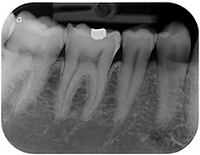

デジタルレントゲンシステム ・ デンタル&パノラマ

従来の単純撮影法X線システムには必ず現像という工程が必要であるため、常に一定の条件で撮影した画像を見ることはできませんでした。

これをデジタル化することにより、常に一定の条件で精細な画像を見ることが出来るようになるばかりではなく、放射線による被曝線量も1/10程度まで減少させることが可能になりました。

パノラマデジタルレントゲン

これはお口の中全体を1度に見るための撮影機器です。

お口の中だけではなく、鼻腔や副鼻腔、顎関節、外耳道、顎骨、下歯槽管、歯槽骨などお口を中心として目の下から首の上までが撮影できます。